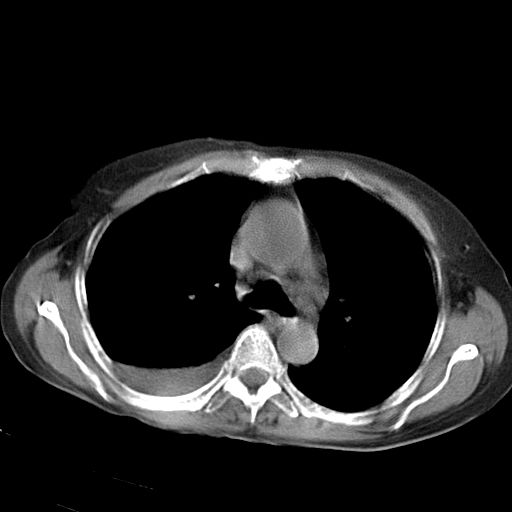

以下是引用jiazh在2006-12-7 20:37:00的发言:[br]肝脏周围半狐形低密度影,肝脏表面受压推移,考虑膈下脓肿可能性大;2、右侧胸腔积液

以下是引用拾荒者在2006-12-7 21:44:00的发言:[br]肝内外胆管多发结石,右膈下多发脓肿,右胸膜腔及叶间裂积液,左肾囊肿。[br] [br]